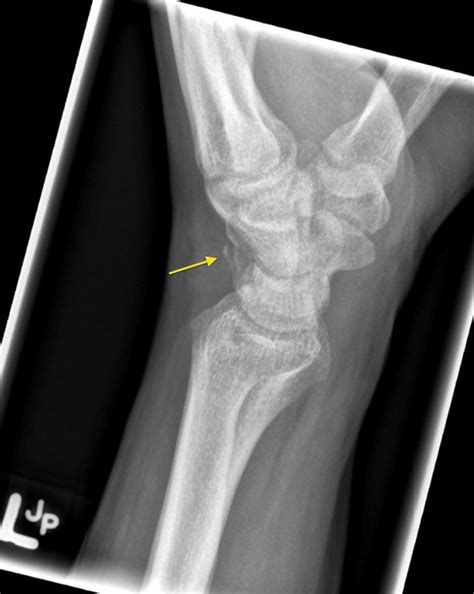

Pisiform fracture | Radiology Case | Radiopaedia.org

Pisiform fracture | Radiology Case | Radiopaedia.org from images.radiopaedia.org

Simultaneous fracture and dislocation of the pisiform has only been described twice in children 1. The pisiform bone is a sesmoid bone, or a small bone within a tendon that increases the pulley action of the muscle. For few weeks, then splint if you have no more see hand doc:

Bone fractures, commonly known as broken bones, happen to millions of people across the country each year. They are only thought to account for ~0.2% of all carpal fractures. Causes vary and treatment is dependent upon the type of fracture. 50% occur in association with other carpal fractures or distal radius fractures. Semantic scholar extracted view of isolated fracture of the pisiform bone. by b a lalanne. This disturbs the structure and strength of the bone, and leads to pain, loss of function and sometimes bleeding and injury around the site. The study of fracture of pisiform bone of wrist has been mentioned in research publications which can be found using our bioinformatics tool below. The two patients were treated with closed reduction of both the distal radius and dislocated pisiform under general anaesthesia. It is the most common carpal bone to break (fracture). The two patients were treated with closed reduction of both the distal radius and dislocated pisiform under general anaesthesia. The most common broken bones are stress fractures, rib fractures, skull fractures, hip fractures, and fractures in children. Explore more on fracture of pisiform bone of wrist below! 50% occur as isolated injuries. The pisiform bone is a sesmoid bone, or a small bone within a tendon that increases the pulley action of the muscle. Quizlet is the easiest way to study, practise and master what you're learning. Bone fractures, commonly known as broken bones, happen to millions of people across the country each year. Simultaneous fracture and dislocation of the pisiform has only been described twice in children 1.